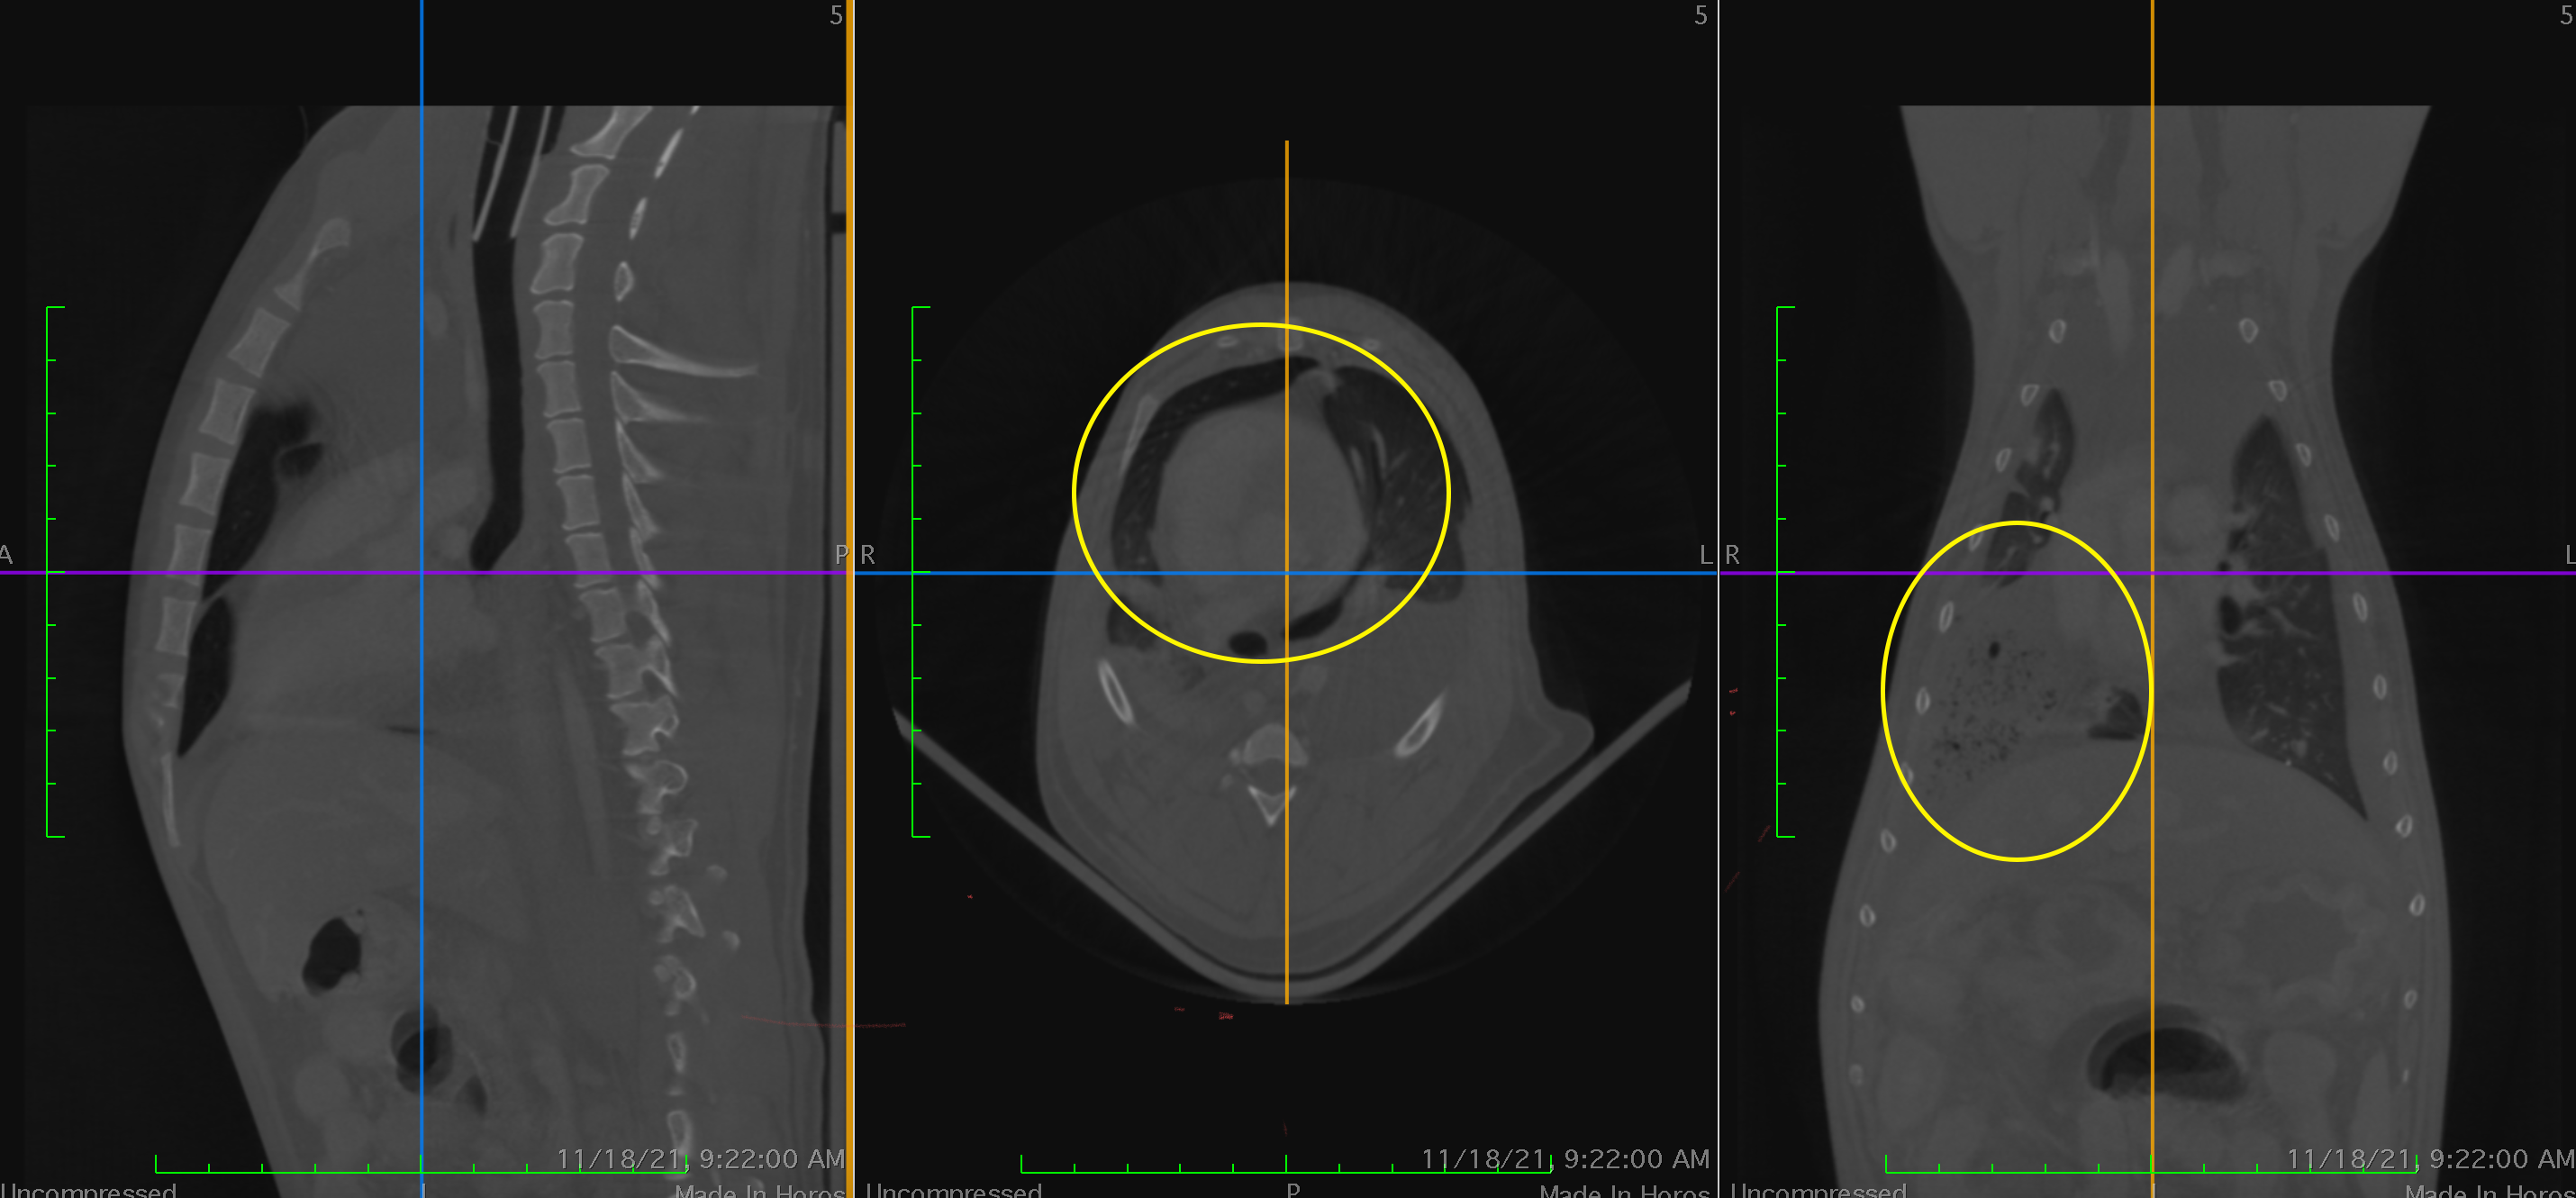

Standiford Veterinary Center strives to provide our patients with the highest level of care. One of the many advanced medical services provided is Computed Tomography or CT scan. CT takes numerous thin “slices” (or X-rays) of the area of interest and then reconstructs the data mathematically into a highly sophisticated and detailed 3-D representation. This scan can be rotated allowing the bones, soft tissue, and vascular structures to be isolated and individually evaluated. Contrast media can be included to markedly improve imaging accuracy and sensitivity.

Most patients are referred for advanced CT imaging when routine diagnostics such as ultrasound or radiographs cannot accurately provide the information needed for a diagnosis or prognosis. CT is exceptional in detecting changes in bones, joints, and cavities or sinuses in the head including the inner ear. The CT also visualizes the spine, chest, lungs, and abdomen. Again contrast agents can provide a detailed map of the blood flow to particular areas such as the liver.